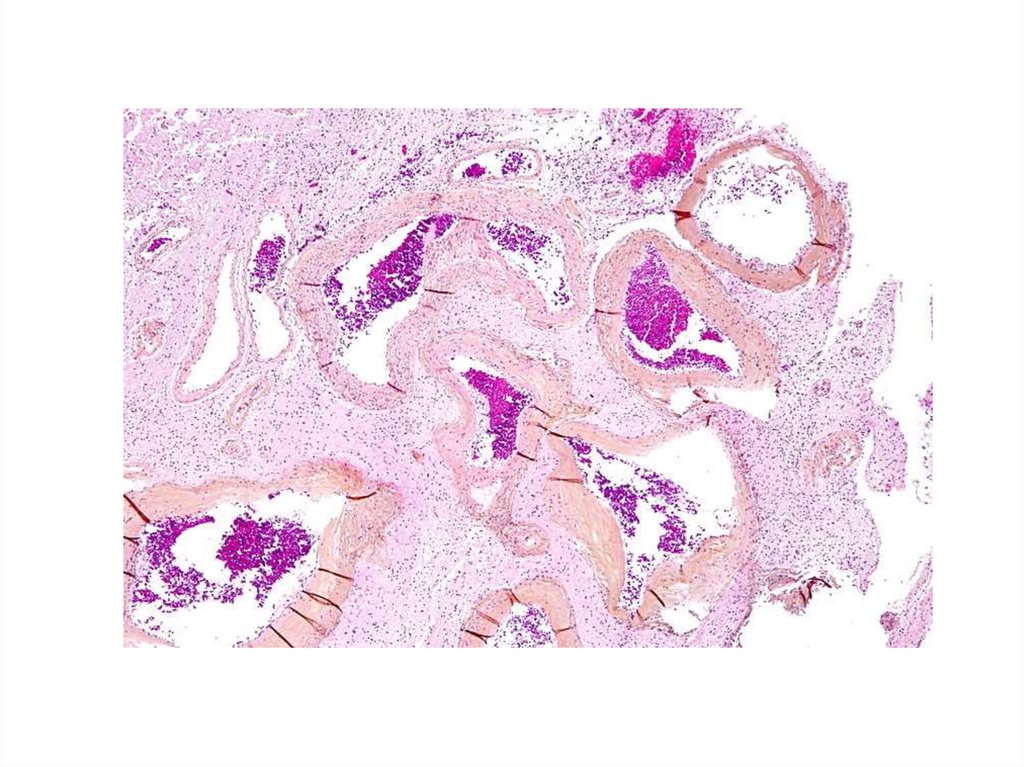

Гистология головного мозга